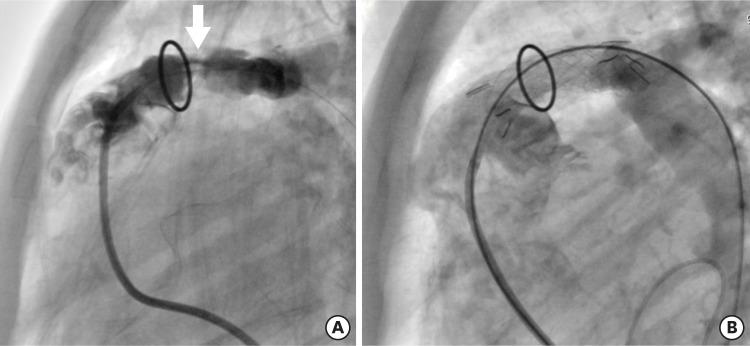

Nine self-expandable stents were implanted in the pulmonary artery, 2 stents in the right ventricle to the pulmonary artery conduit, and 1 stent in the coarctation. The narrowest diameter of the stented vessel increased from 5.7±3.2 mm to 12.6±3.4 mm (p<0.05). The mean pressure gradient across the stenotic lesion decreased from 23.0±28.2 mmHg to 3.2±3.6 mmHg (p<0.05). Distal migration of the stent occurred in 1 patient, and significant neointimal ingrowth was noted in 1 patient.

9个自膨胀支架植入肺动脉,2个支架植入右心室至肺动脉管道,1个支架植入缩窄部位。置入支架血管的最窄直径从5.7±3.2 mm增加到12.6±3.4 mm(p<0.05)。狭窄病变两端的平均压力阶差从23.0±28.2 mmHg降至3.2±3.6 mmHg(p<0.05)。1例患者发生支架远端移位,1例患者出现明显的新生内膜增生。